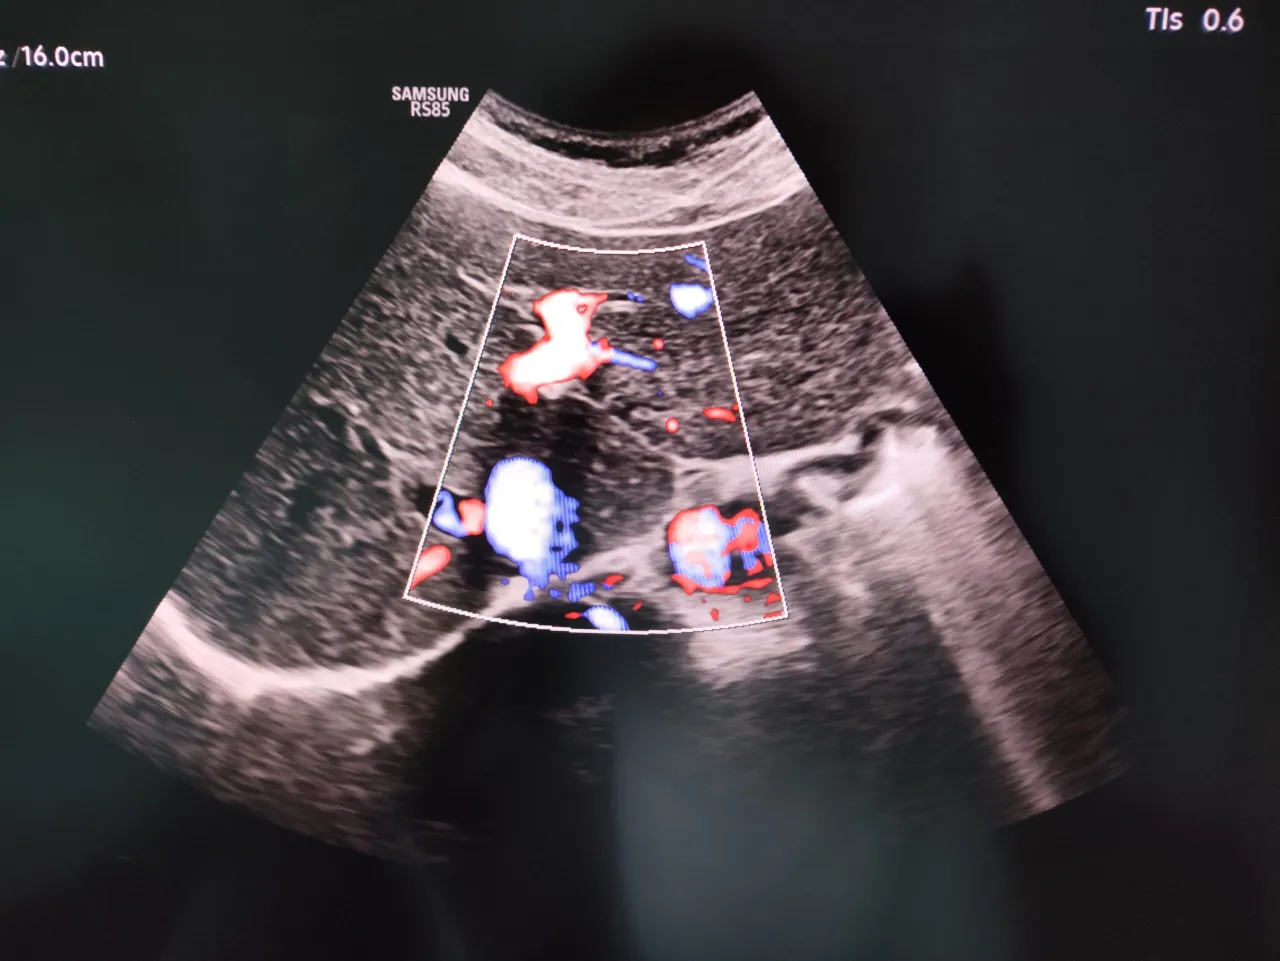

- Duże naczynia krwionośne: Aorta brzuszna (ocena pod kątem tętniaków, miażdżycy), żyła główna dolna.

- Przebieg badania: Lekarz będzie delikatnie przesuwał głowicę ultrasonografu po skórze brzucha, oglądając na monitorze obrazy poszczególnych narządów. Może poprosić o wstrzymanie oddechu na kilka sekund lub o zmianę pozycji (np. na bok), aby uzyskać lepszy widok.

- Uzyskiwanie obrazów i pomiary: Lekarz będzie wykonywał pomiary narządów, oceniał ich strukturę i dokumentował ewentualne zmiany, zapisując obrazy do dokumentacji.